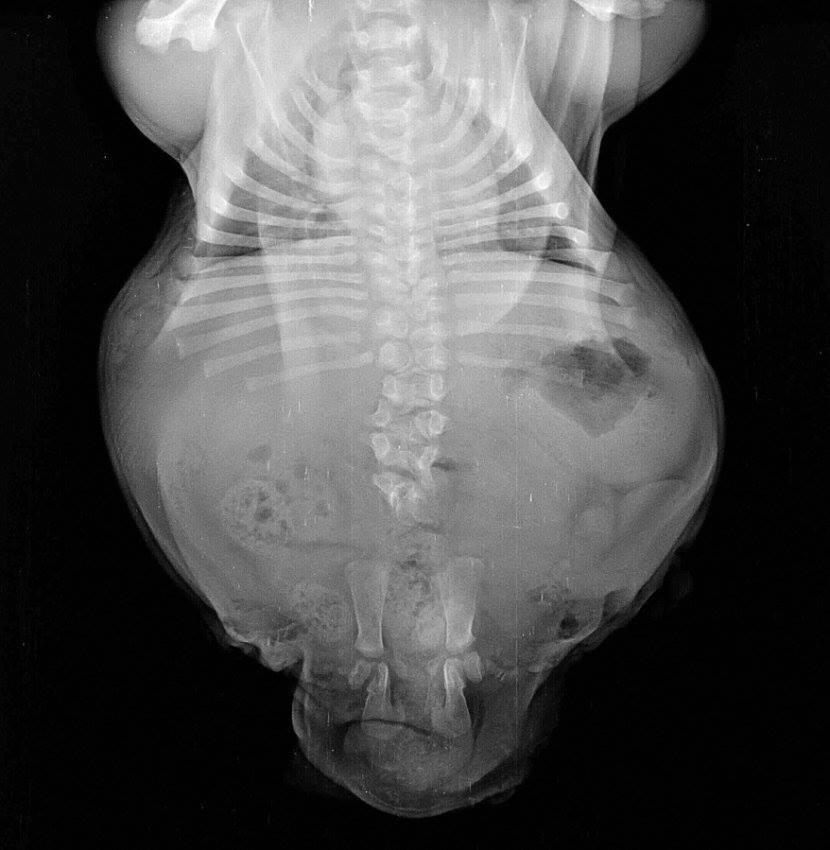

Voici Bonsai à 4 semaines, avec ses pattes arrière atrophiées. À ce stade, personne ne savait s’il allait s’en tirer.

Ses pattes arrière et son bassin ont malheureusement dû être amputés. C’était le seul moyen de le sauver. Mais l'opération s’est bien passée.